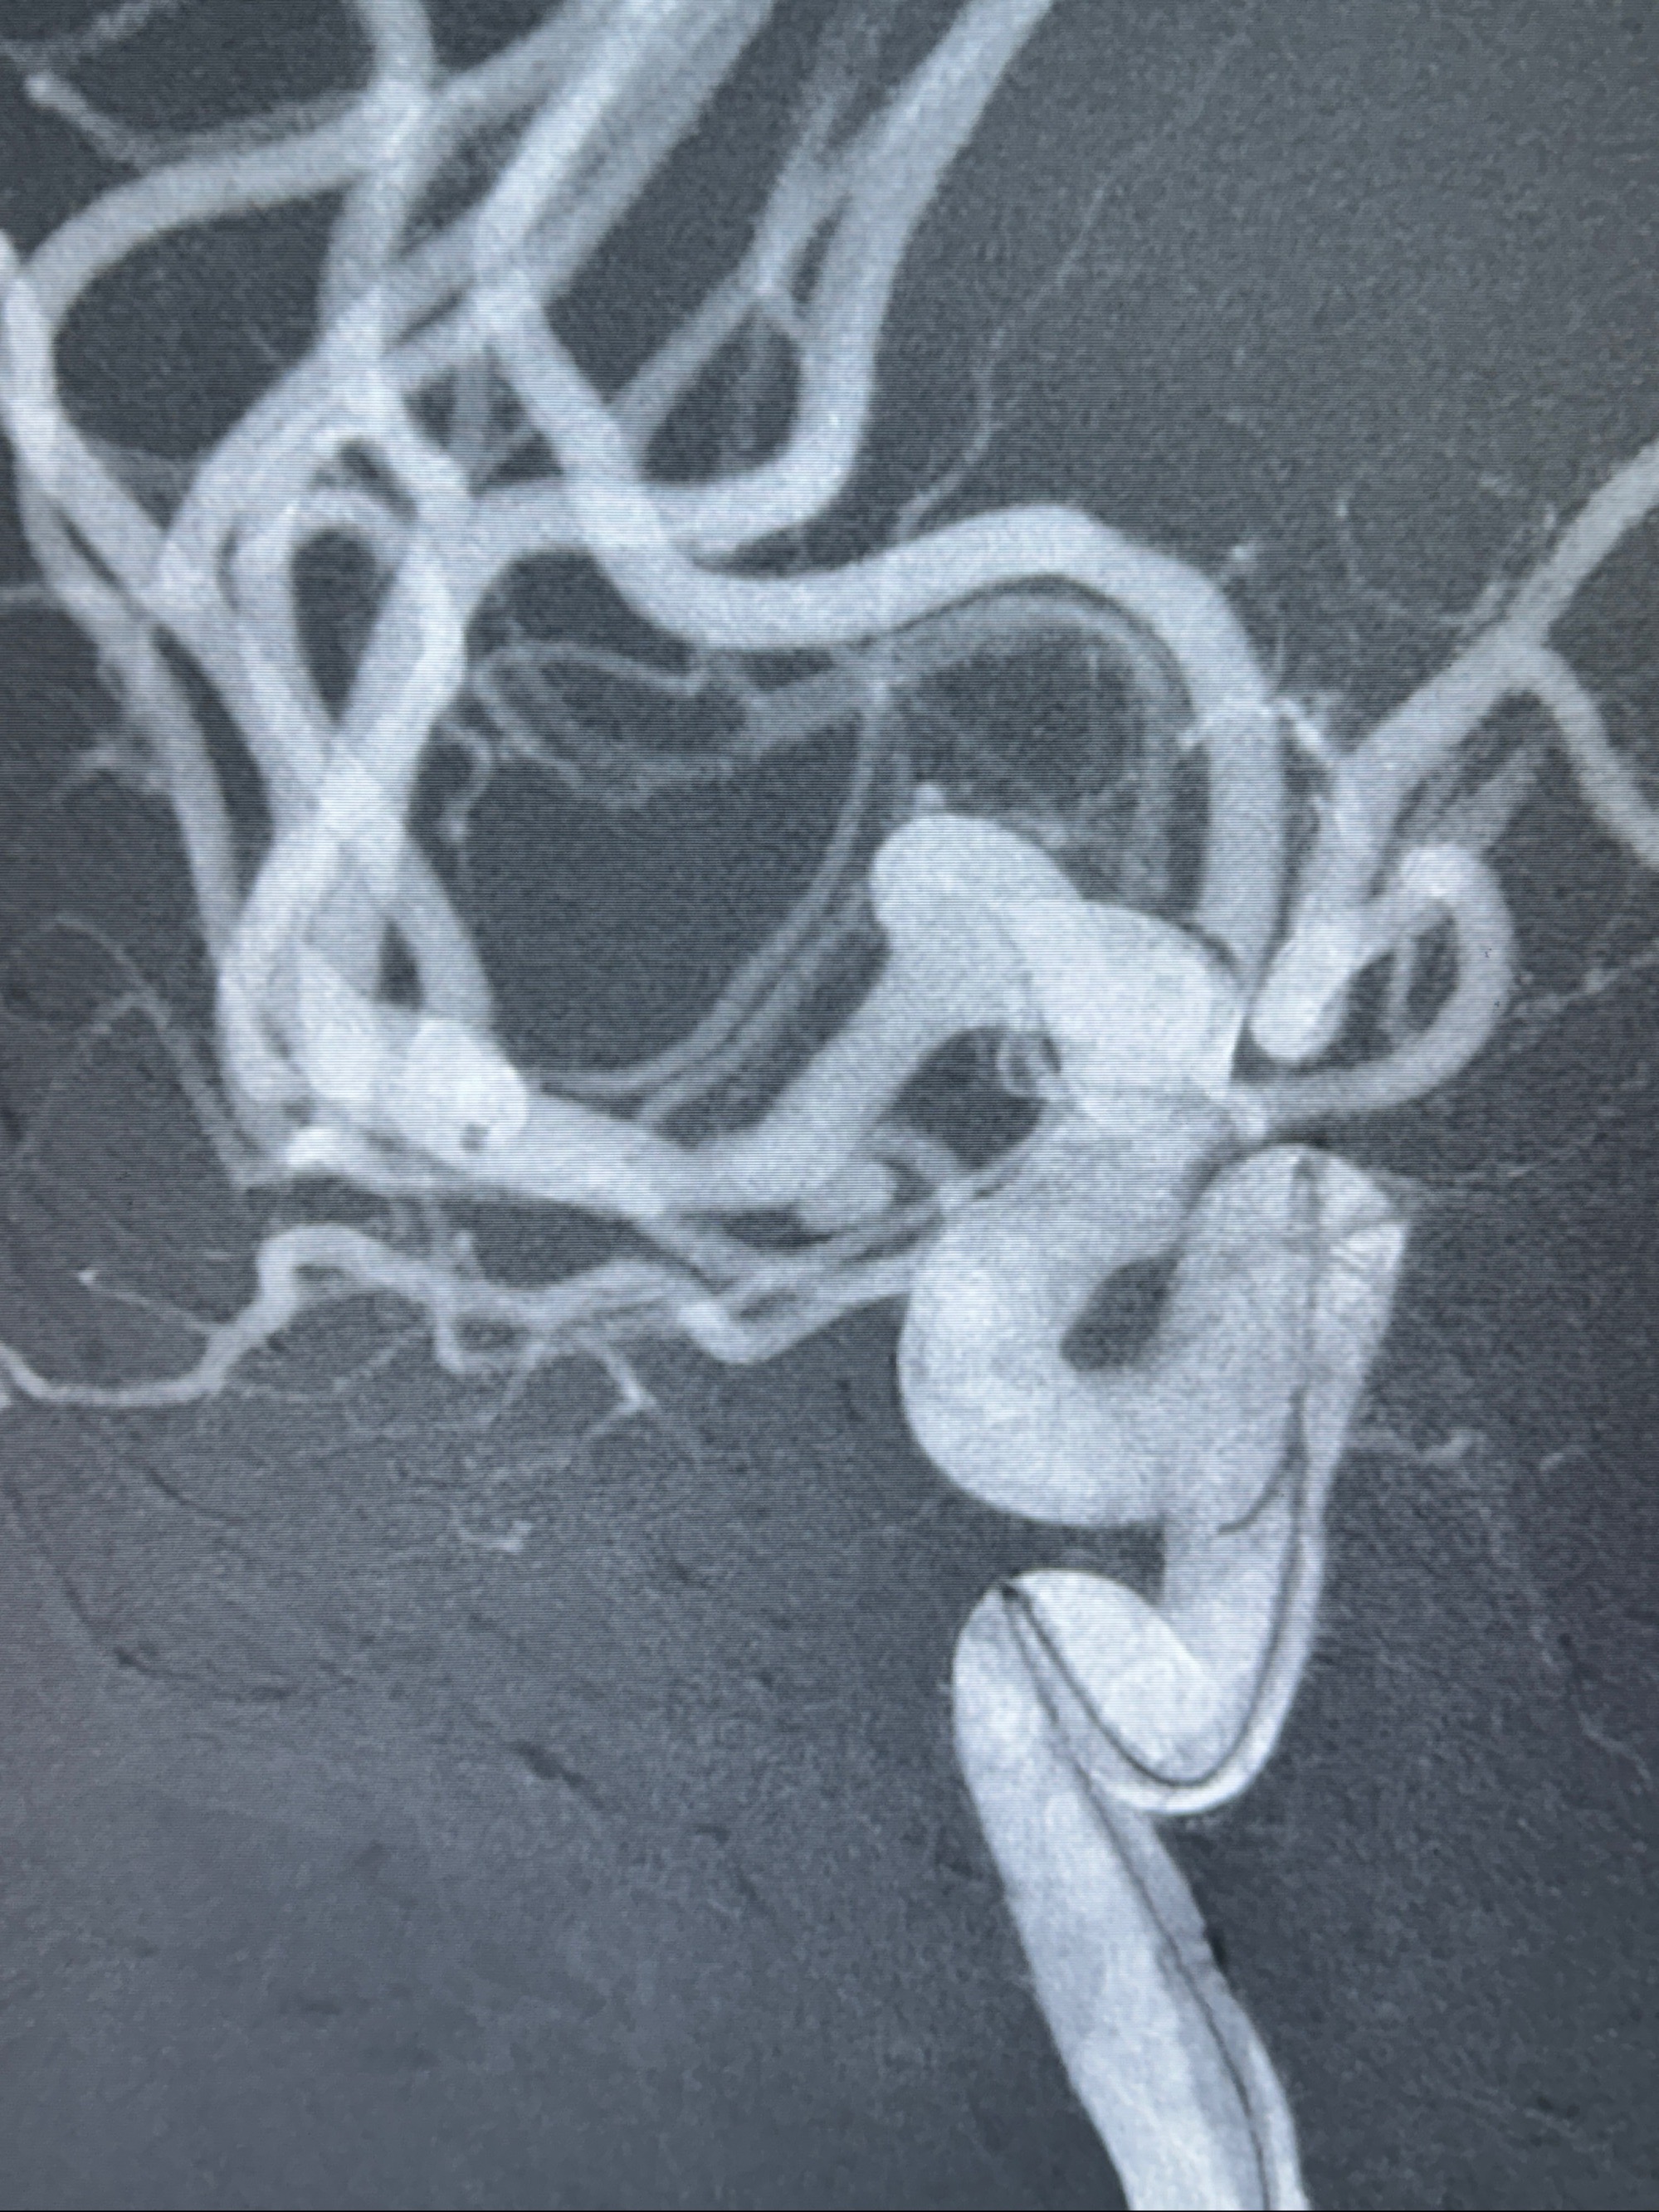

2023-12-04全麻下行支架辅助治疗

S-AB4-20mm

麻醉苏醒佳,遵嘱动作

术后即刻CT